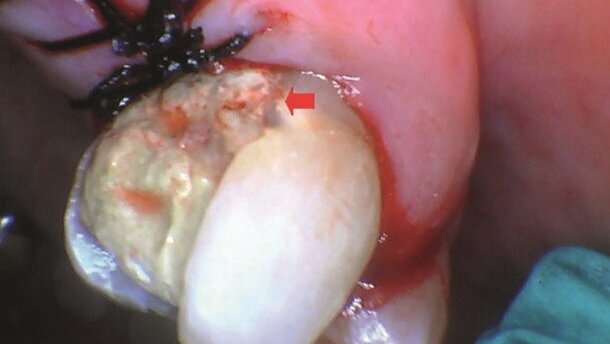

Przypadek ten przedstawia zastosowanie lasera Solea na szkliwie i zębinie. 69-letnia pacjentka zgłosiła się z powodu nadwrażliwości zęba. Badanie wykazało pęknięte wypełnienie amalgamatowe oraz próchnicę wtórną na zębie 27 (Ryc. 1a i b). Mimo, że ząb był żywy, nie podano znieczulenia, ale zastosowano znieczulenie powierzchniowe (TAC 20 zawierający lidokainę 20%, tetrakainę 4%, fenylefrynę 2%) na okolicę powierzchni stycznej przed założeniem formówki/klina. Solea został wykorzystany do zaznaczenia granicy preparacji na ustawieniach dla szkliwa (Enamel Setting), emitując wiązkę do momentu odsłonięcia zębiny: rozmiar plamki 0,25 mm, czas trwania impulsu 15 ps, 100% wykorzystania wody, 20%-100% zmiennej prędkości ze sterownika nożnego.

Następnie amalgamat został usunięty za pomocą turbiny (Kavo Electrotorque) oraz wiertła 245. Możliwa była swobodna praca wiertłem ze względu na efekt głębokiego znieczulenia uzyskany dzięki rozpoczęciu pracy od lasera Solea. Kontynuowano opracowywanie ubytku z użyciem Solea na ustawieniach dla szkliwa (Enamel Setting): rozmiar plamki 1,00 mm, czas trwania impulsu 15 ps, 100% wykorzystania wody, 10%-100% zmiennej prędkości ze sterownika nożnego. Opracowano i usunięto próchnicę za pomocą Solea na ustawieniach dla zębiny (Dentin Setting): rozmiar plamki 1,00 mm, czas trwania impulsu 70 ps, 100% wykorzystania wody 20%-100% prędkości zmiennej ze sterownika nożnego. By dokończyć preparację, brzegi ubytku zostały wygładzone wiertłem diamentowym (Ryc. 2). Do przygotowania zęba do odbudowy użyto Scotchbond Universal (3M). Warstwę XFlow (DENTSPLY) o grubości ok. 0,5 mm nałożono na proksymalną powierzchnię dodziąsłową. Odbudowę zakończono materiałem Tetric EvoCeram Bulk Fill (Ivoclar Vivadent) oraz polerolwaniem powierzchni (Ryc. 3 i 4).